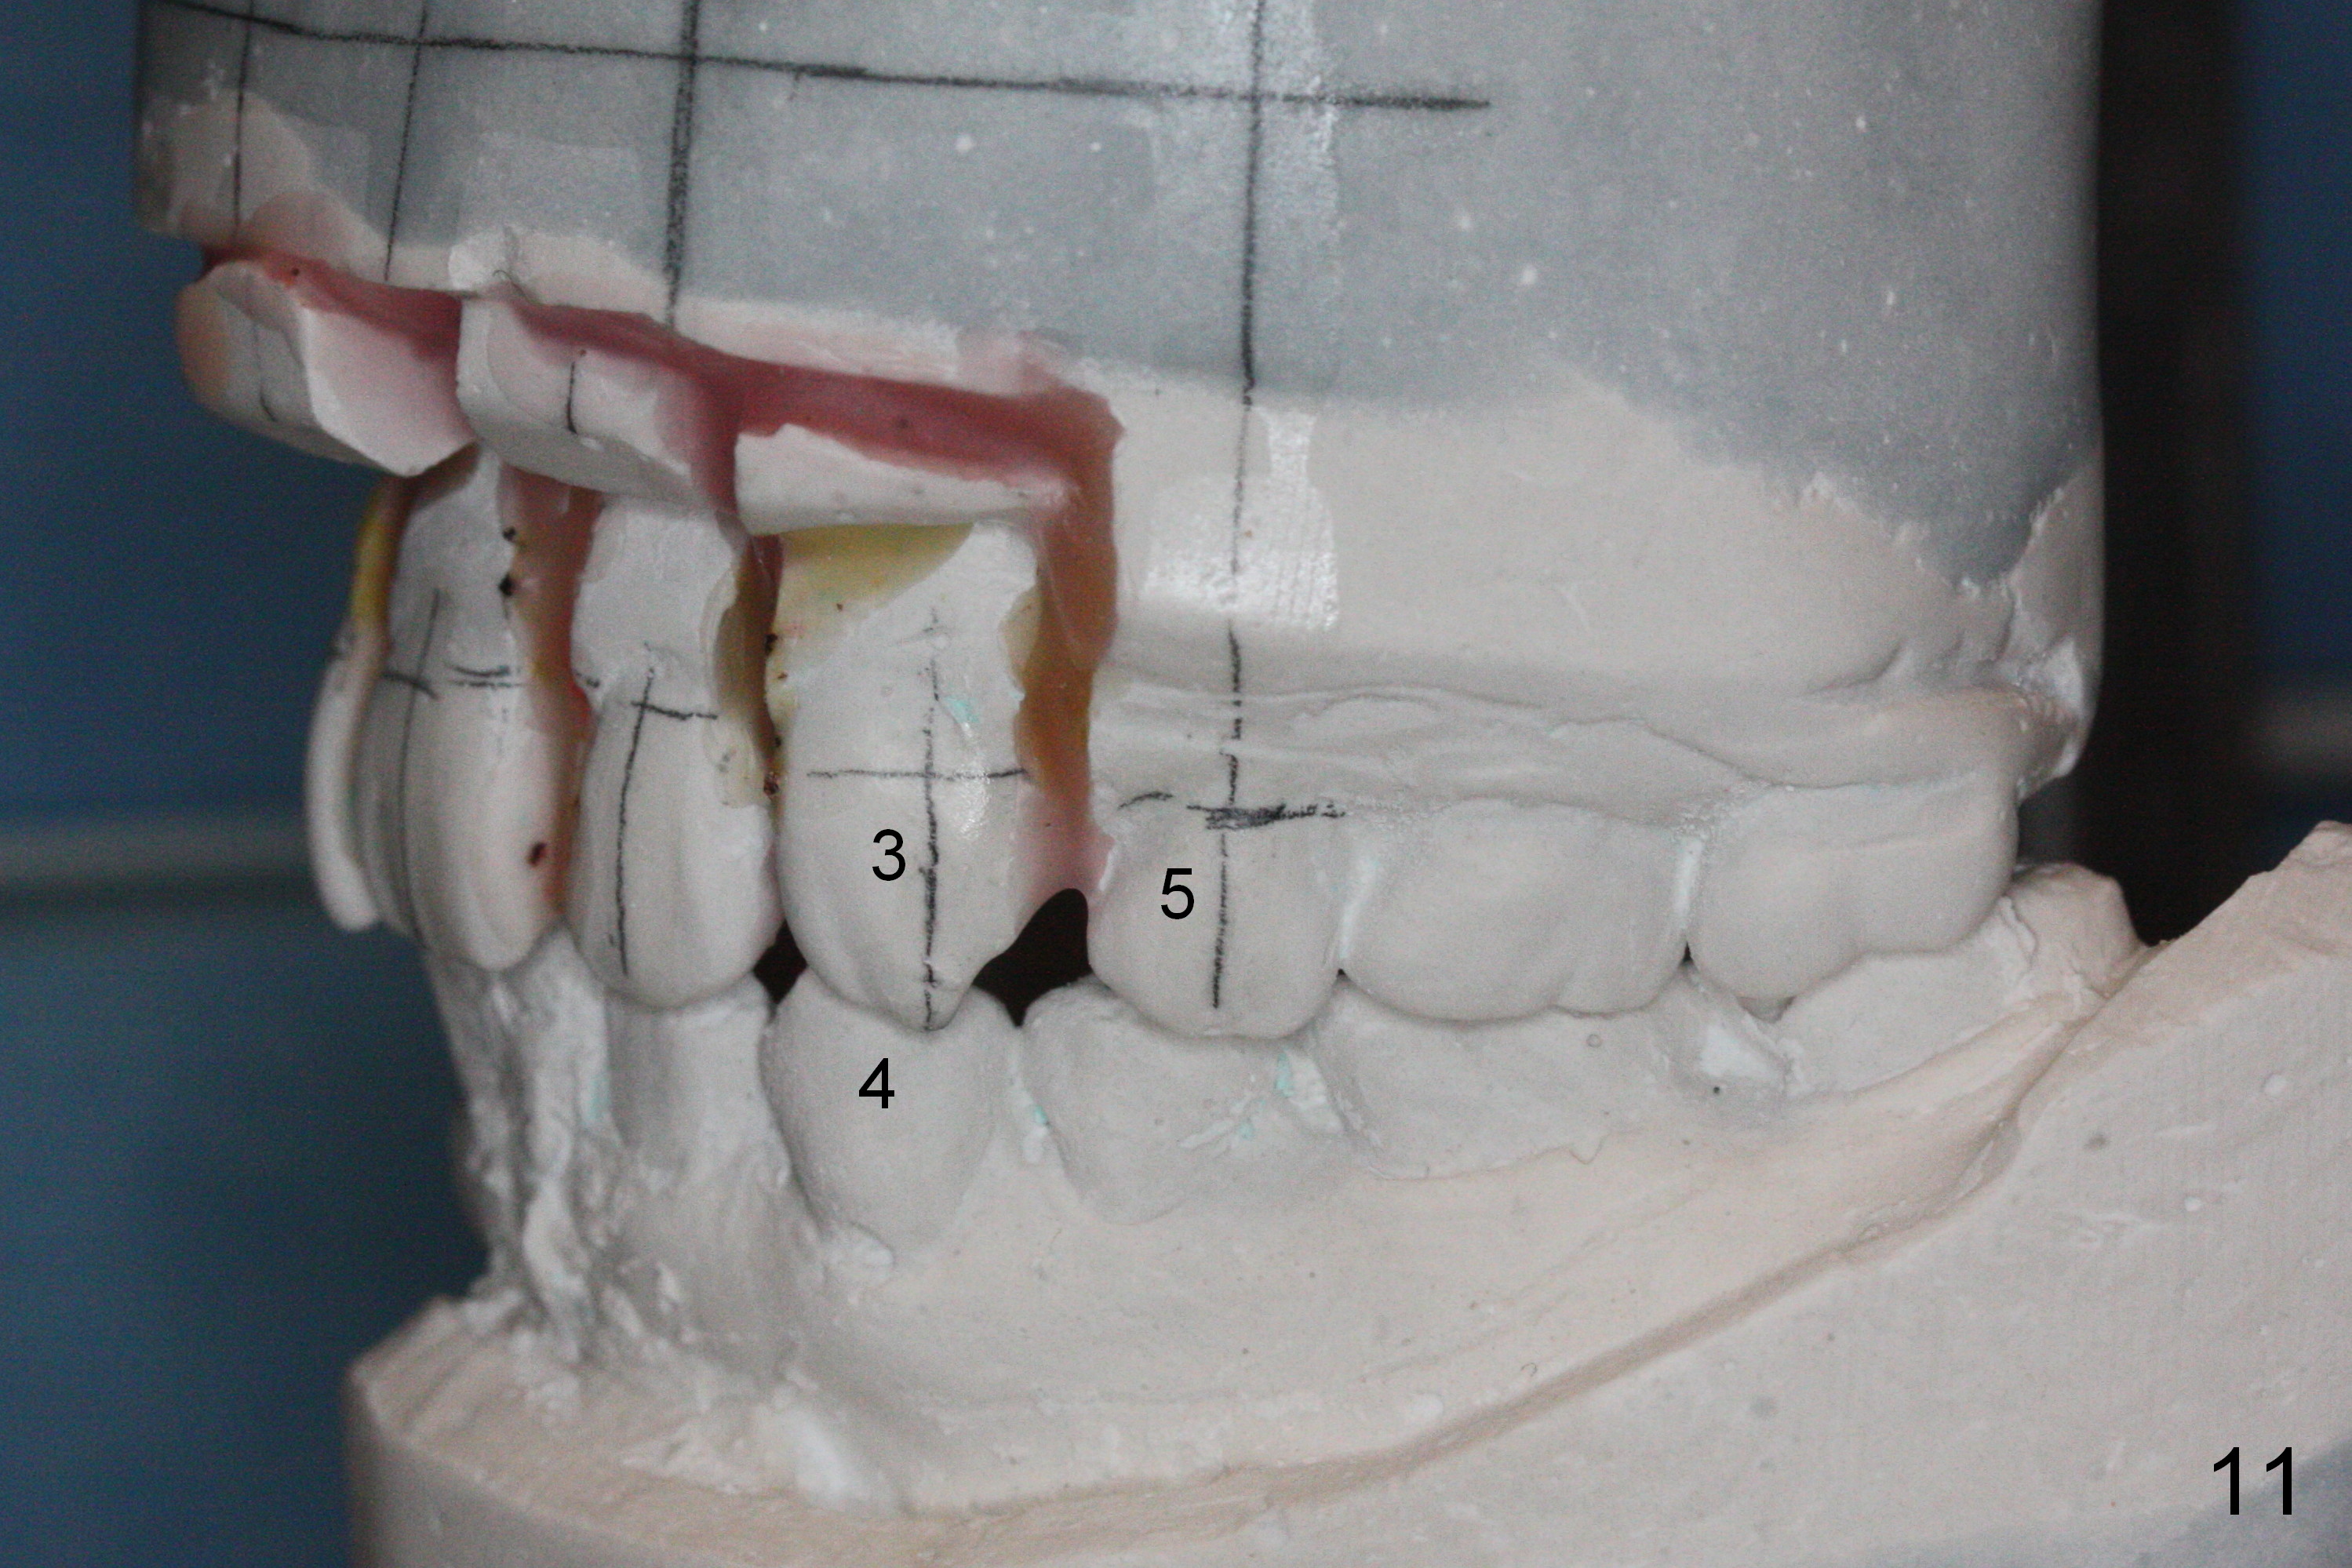

Wax up shows that there are diastemata between the upper teeth after U4s' extraction (Fig.9-11). It appears that L3s should be reduced as the incisors and that the upper posterior teeth should be mesialized. In that case, the mini-implants may be not needed.

The rotation of the upper canines is not corrected much in the next 3.5 months (Fig.21, as compared to Fig.18). Distalization of the upper right canine is implemented by power chain, but this is not sufficient because of the anterior deep bite. Note the tension of 18 niti wire between LR 3 and 4 (^). Mini implants are going to be placed mesial or distal to L3s (Fig.22,23 circles) to intrude the lower anterior teeth with elastic or power chain (Fig.23 red line, 24 black area). The upper anteriors will have space to be distalized (Fig.24 arrow). If necessary, proximal reduction will be accomplished at LR3 (extra wide, Fig.25 black outline) for further overjet correction (arrows).